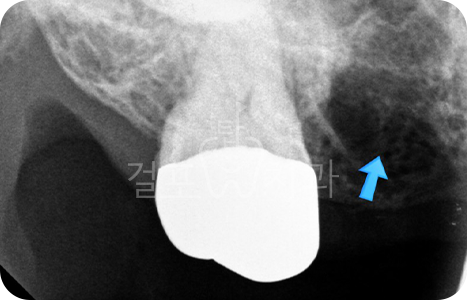

• 치아 뽑은 자리 잇몸염증이 매우 심한 상태였습니다. 잇몸상태가 좋지 않아도

발치 즉시 임플란트를 시도할 수 있습니다. 다만, 2~3달 지난 후 수술한다면 더 안전하므로 이런 경우 즉시 식립을 추천드리지 않습니다. 발치 몇 달 후 상악동 거상술과 뼈이식 임플란트를 함께하여 수술을 완료하였습니다.